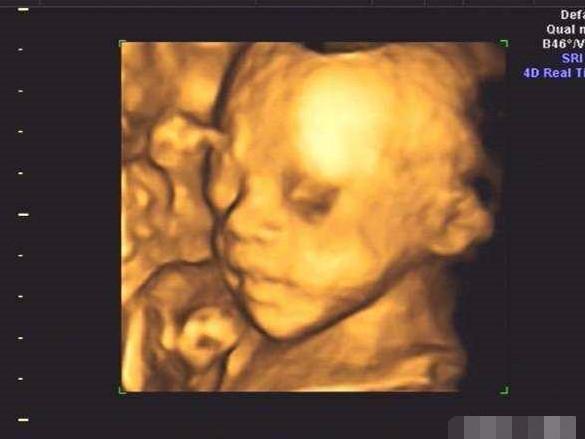

今天四维大排畸归来,医生说一切正常,终于放心了。宝宝超级配合,二十分钟就过了,贴心小棉袄,一看照片就觉得像女宝,熟人告诉我宝宝像妈妈,喜得小公主一枚,下面我就把我怀孕的一些症状整理分享给大家,接女宝宝啦!

秀秀我的小棉袄

四维